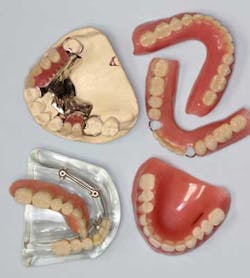

Dentures and partial dentures are treatment options that are an acceptable way to replace function and missing teeth. Unfortunately, many practitioners find the creation of said prostheses frustrating and difficult. Not only can the fabrication be challenging, but, statistically, these populations of patients have the highest percentage of dental complaints. Why? Because the loss of the problematic natural teeth is often considered a way to eliminate dental woes. Instead, a removable prosthesis is actually an introduction into a new realm of challenges. Regardless of these concerns, when treatment planned and fabricated correctly, the outcome for partials and dentures can be predictable.

2. Discuss ALL restorative and replacement options — have models available showing implants, partials, dentures, bridges, etc. As oral health-care providers, it is our job to diagnose and then present ways to restore form and function. Educating the patient allows for a good patient/provider relationship and ultimately a better long-term outcome.

5. For large spans or for full edentulism, make interim dentures/partials. By allowing the tissue and bone to heal properly, the stage is set for a better-fitting definitive prosthesis. It also gives patients an “extra set” should they lose or break their final denture/partial down the road.